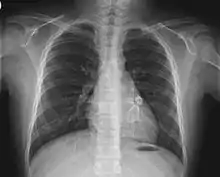

Cardiac

Heart complications are the most important aspect of Kawasaki disease, which is the leading cause of heart disease acquired in childhood in the United States and Japan.[29] In developed nations, it appears to have replaced acute rheumatic fever as the most common cause of acquired heart disease in children.[13] Coronary artery aneurysms occur as a sequela of the vasculitis in 20–25% of untreated children.[50] It is first detected at a mean of 10 days of illness and the peak frequency of coronary artery dilation or aneurysms occurs within four weeks of onset.[46] Aneurysms are classified into small (internal diameter of vessel wall <5 mm), medium (diameter ranging from 5–8 mm), and giant (diameter > 8 mm).[29] Saccular and fusiform aneurysms usually develop between 18 and 25 days after the onset of illness.[13]

- Echocardiogram may show subtle coronary artery changes or, later, true aneurysms.

- Angiography was historically used to detect coronary artery aneurysms, and remains the gold standard for their detection, but is rarely used today unless coronary artery aneurysms have already been detected by echocardiography.